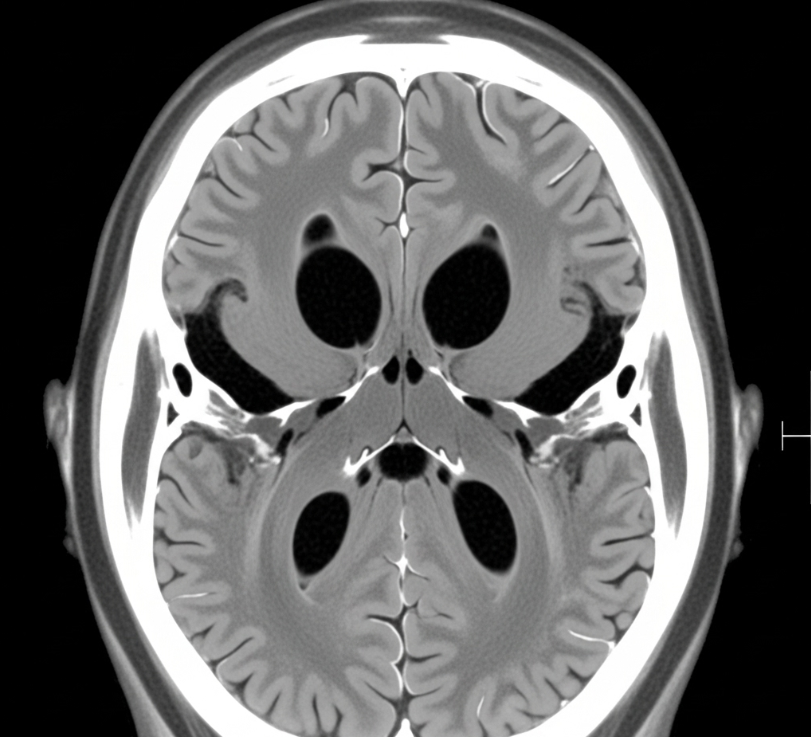

Case Study of NMDA Encephalitis in an 18-Year-Old Female With No Underlying Etiolog.

Sabina Nayab1, Qasim Bashir2, Adnan Aslam3, Amina Saeed khan4

Pages: 4-10